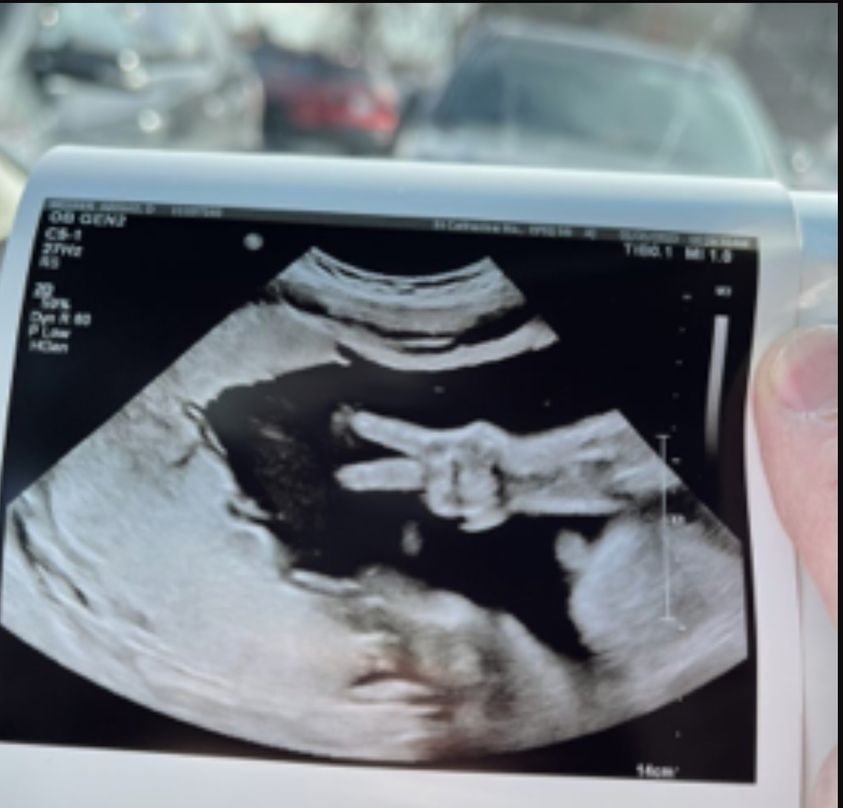

美國印第安納州一名懷孕31週的婦女艾比維納(Abby Weener),日前和丈夫凱爾維納(Kyle Weener)到醫院產檢時,在進行超音波照時居然出現有趣畫面,腹中寶寶好像知道父母和醫生正在看她,竟突然舉起手比出「V」的手勢,讓在場所有人都感到不可思議、太奇妙了。

由於照片實在太特別,也讓一些人不敢相信是真的或是修圖效果?即將成為三寶媽的艾比貼出一張在寶寶的臉、頭髮、手指、手臂上都做了註記的照片,她表示,醫院人員是拍完了這張照片後,又趕快回去擷取照片,在很快速的時間裡捕捉到了寶寶比YA的瞬間。

艾比說,醫護人員直呼是第一次看到這樣的畫面,這是非常獨一無二的。他們夫妻都是虔誠的基督徒,認為女兒是上帝送給他們最棒的禮物,這個舉動像似在跟他們說:「我過得很好,正在媽媽的肚子裡健康長大。」